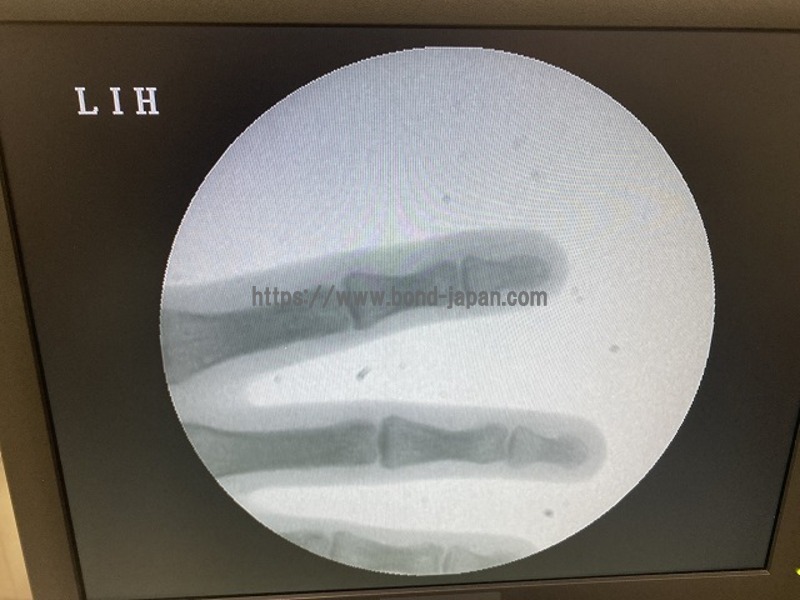

C-arm

SIMADZU

OPESCOPE ACTIVO WHA-200

*Surgical Mobile C-arm.

SIEMENS

Siremobile Compact L

*Compact all-rounder C-arm for surgical imaging.

Mobile C-Arm

CANON

SXT-1000A